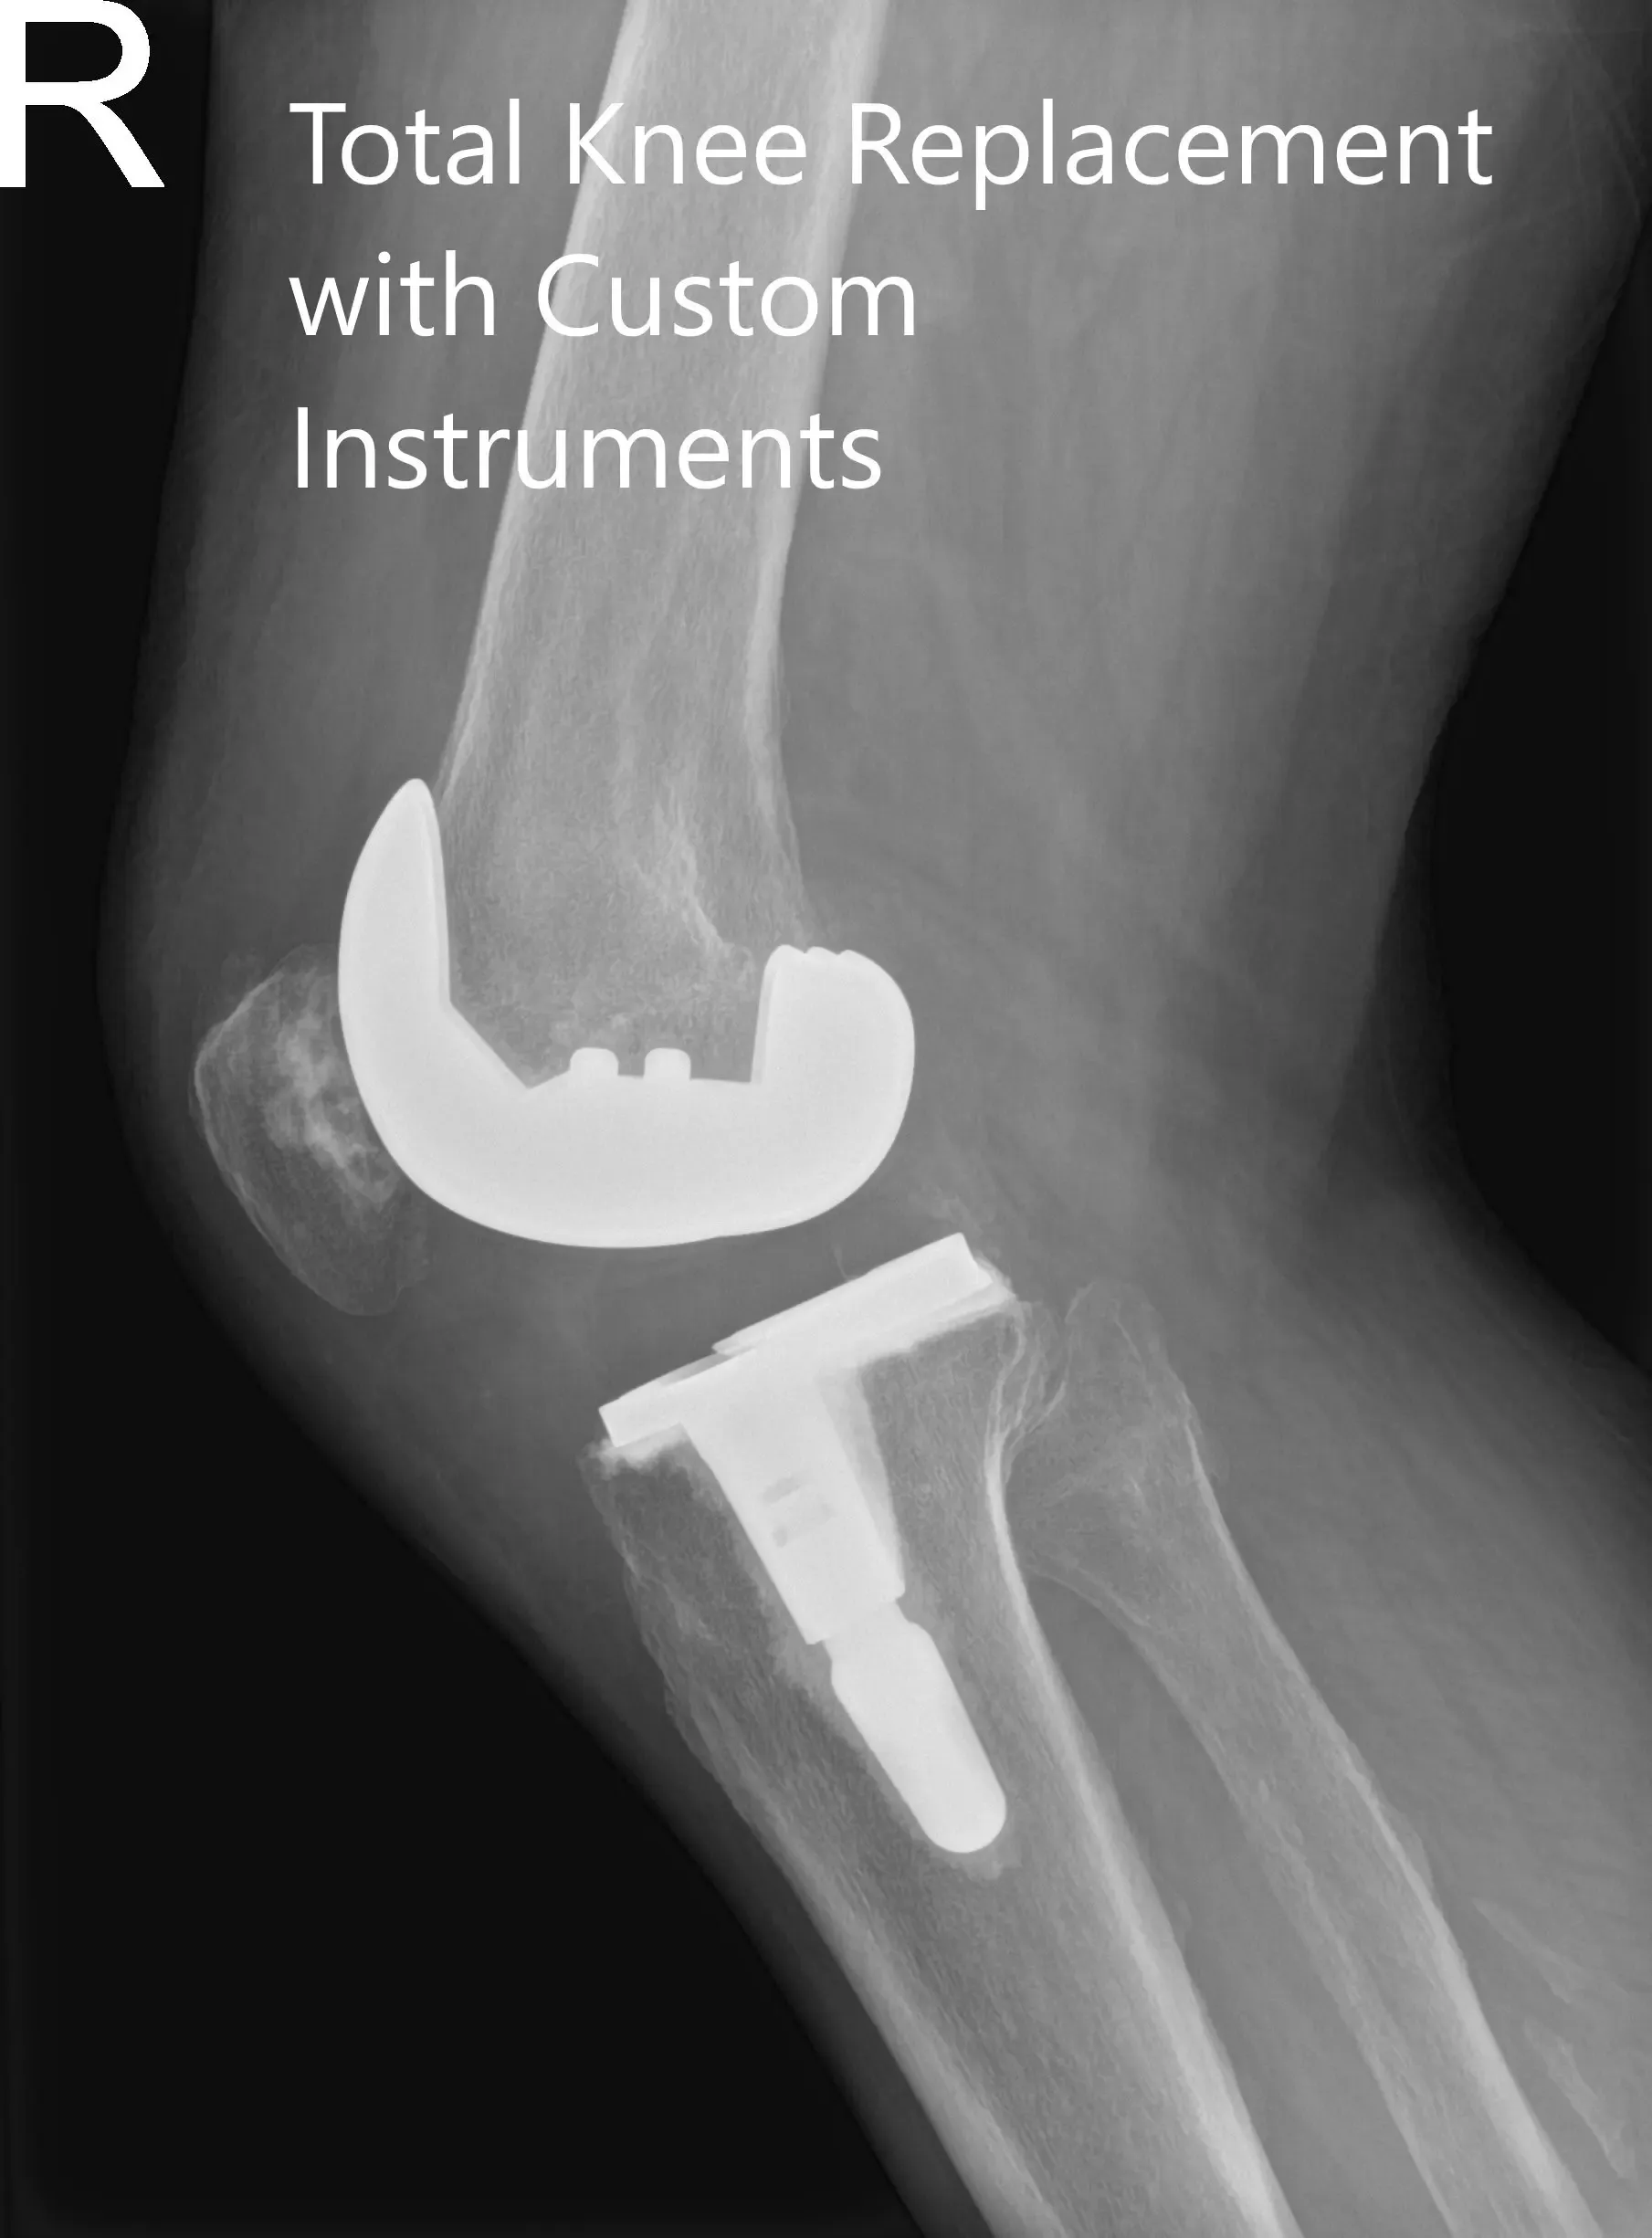

IMPLANTES UTILIZADOS: Estabilización posterior, 10 componentes femorales estándar derecho lado derecho con tibia F izquierda cementada con tallo de 14 x 30 y poli de 16 mm y una rótula polirótula de 32 x 8,5 mm de diámetro.

Radiografía postoperatoria de la rodilla derecha en vistas anteroposterior y lateral.